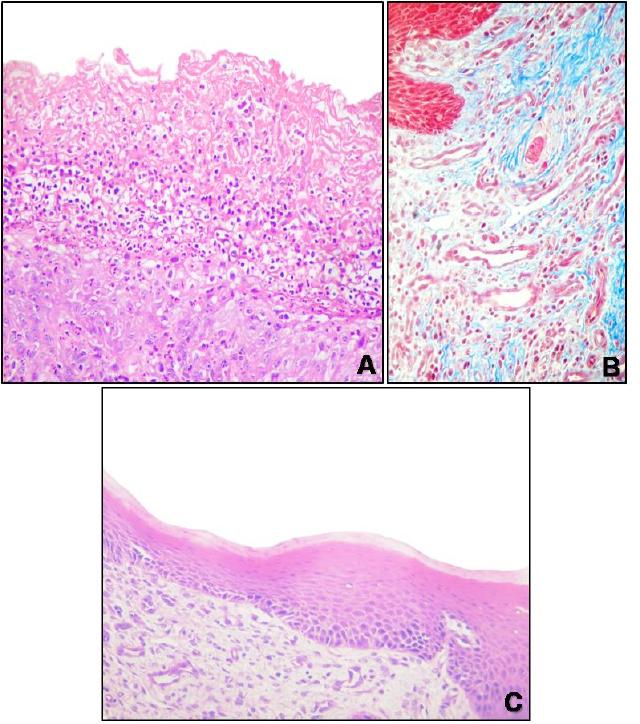

FIGURA 12– Superfície dorsal da língua. A) Observa-se área difusa de ulceração, Bovino 2,

Hematoxilina-eosina (HE), obj. 20x. B) Tecido fibrovascular subjacente à região parcialmente

ulcerada da superfície dorsal da língua, Bovino 9. Observa-se grande quantidade de tecido

conjuntivo rico em fibras de colágeno (coradas em azul) e numeroso vasos neoformados (em

vermelho), Tricrômico de Masson, obj. 40x. C) Epitélio dorsal, língua, Bovino 6. Observa-se

área de re-epitelização caracterizada por um fino epitélio que recobre área de tecido

fibrovascular, HE, obj. 4x.........................................................................................................53!